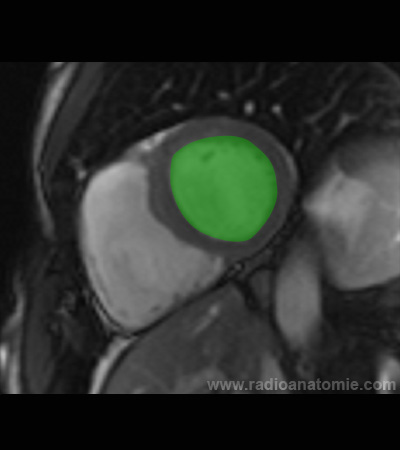

Radioanatomie et plans de coupe en IRM cardiaque

Ventricule gauche

Ventricule droit

Septum interventriculaire